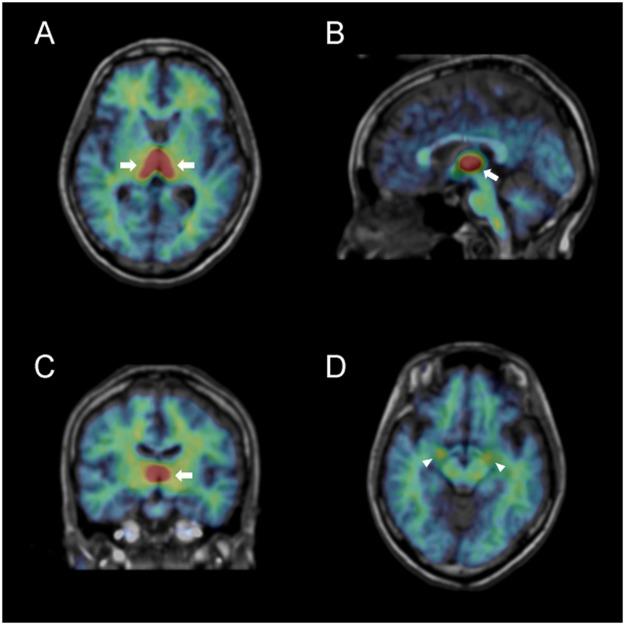

Aromatase, an enzyme that converts androgens to estrogens, has been reported to be involved in several brain functions, including synaptic plasticity, neurogenesis, neuroprotection, and regulation of sexual and emotional behaviours in rodents, pathophysiology of Alzheimer's disease and autism spectrum disorders in humans. Aromatase has been reported to be involved in aggressive behaviours in genetically modified mice and in personality traits by genotyping studies on humans. However, no study has investigated the relationship between aromatase in living brains and personality traits including aggression. We performed a positron emission tomography (PET) study in 21 healthy subjects using C-cetrozole, which has high selectivity and affinity for aromatase. Before performing PET scans, subjects answered the Buss-Perry Aggression Questionnaire and Temperament and Character Inventory to measure their aggression and personality traits, respectively. A strong accumulation of C-cetrozole was detected in the thalamus, hypothalamus, amygdala, and medulla. Females showed associations between aromatase levels in subcortical regions, such as the amygdala and supraoptic nucleus of the hypothalamus, and personality traits such as aggression, novelty seeking, and self-transcendence. In contrast, males exhibited associations between aromatase levels in the cortices and harm avoidance, persistence, and self-transcendence. The association of aromatase levels in the thalamus with cooperativeness was common to both sexes. The present study suggests that there might exist associations between aromatase in the brain and personality traits. Some of these associations may differ between sexes, while others are likely common to both.

芳香酶是一种将雄激素转化为雌激素的酶,已被报道参与多种大脑功能,包括突触可塑性、神经发生、神经保护以及调节啮齿动物的性行为和情绪行为、阿尔茨海默病和自闭症谱系障碍的病理生理学。芳香酶已被报道参与基因修饰小鼠的攻击行为以及人类基因分型研究中的人格特征。然而,尚无研究调查活体大脑中的芳香酶与包括攻击行为在内的人格特征之间的关系。我们在 21 名健康受试者中进行了正电子发射断层扫描(PET)研究,使用 C-他莫昔芬,其对芳香酶具有高选择性和亲和力。在进行 PET 扫描之前,受试者回答了 Buss-Perry 攻击问卷和气质与性格量表,分别测量他们的攻击行为和人格特征。在丘脑、下丘脑、杏仁核和延髓中检测到 C-他莫昔芬的强烈积累。女性表现出皮质下区域(如杏仁核和下丘脑视上核)芳香酶水平与攻击、新奇寻求和自我超越等人格特征之间的关联。相比之下,男性表现出皮质芳香酶水平与回避、坚持和自我超越之间的关联。丘脑芳香酶水平与合作性之间的关联对两性都很常见。本研究表明,大脑中的芳香酶可能与人格特征存在关联。其中一些关联可能在性别之间存在差异,而另一些则可能对两性都很常见。